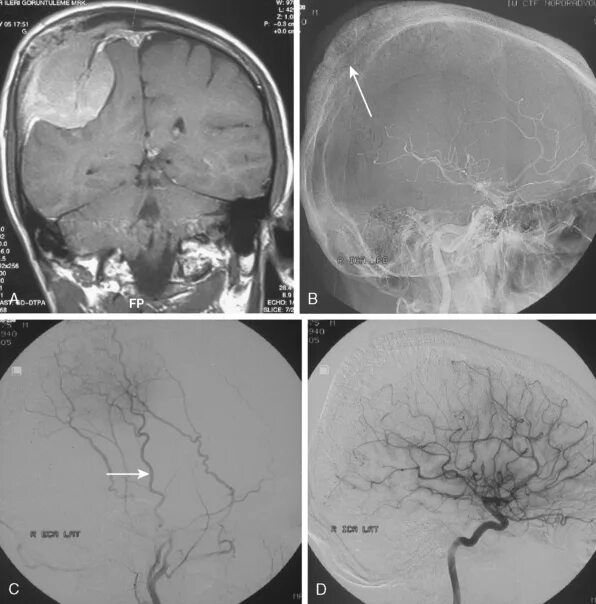

Менингиомы головного мозга мкб